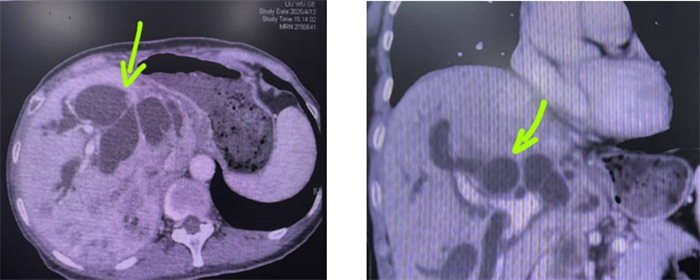

术前CT(正位、侧位)显示:肝门部胆管细胞癌并肝内外胆管扩张明显